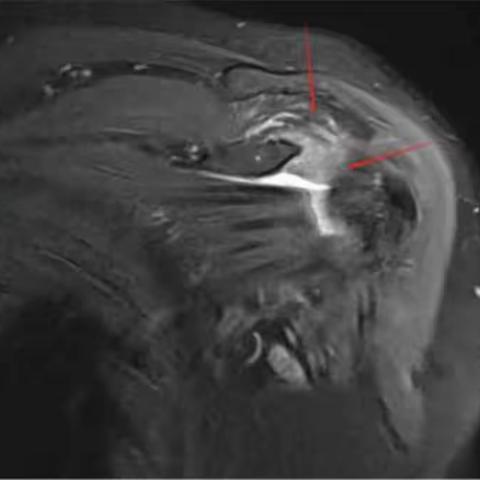

粘连性肩关节炎

2023-10-15 477阅读